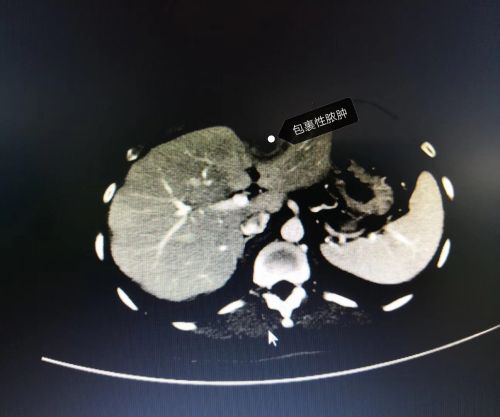

ct片上可以看到明显的肿块。

医生推断,条状高密度影应该是鱼刺。

鱼刺被周围组织包裹,在胃和肝之间形成一个巨大脓肿。(易为民

入院后,医生进行体查发现,李女士上腹部隆起和压痛都很明显,CT检查发现,在她的肝和胃之间有一个低密度病灶,其中还有一个条状物体。患者表示,近一年来,腹部一直隐隐作痛,洗澡时还可以摸到肚子里“有一坨东西”,最近时常出现发烧、畏寒的情况。

据此分析讨论后,肝胆综合科彭创、易为民教授,以及杨平洲主任医师、刘昌军副主任医师等专家认为,应该是一根鱼刺经口腔、咽喉、食道进入胃,然后从胃壁穿出,在李女士的肝和胃之间“扎下根”,由于时间太久,鱼刺被周围组织包裹、感染而形成脓肿。

9月7日,易为民、杨平洲、刘昌军等医务人员为李女士进行手术探查,在患者的肝和胃之间发现一个8×8×6cm3的脓肿,一根约2.5cm长的鱼刺赫然在其中,证实了医生术前的判断。完整切除脓肿,彻底清洗腹腔后,手术顺利完成。预计住院费用在6万元左右,李女士表示:“这么贵的鱼肯定这辈子都记得!”